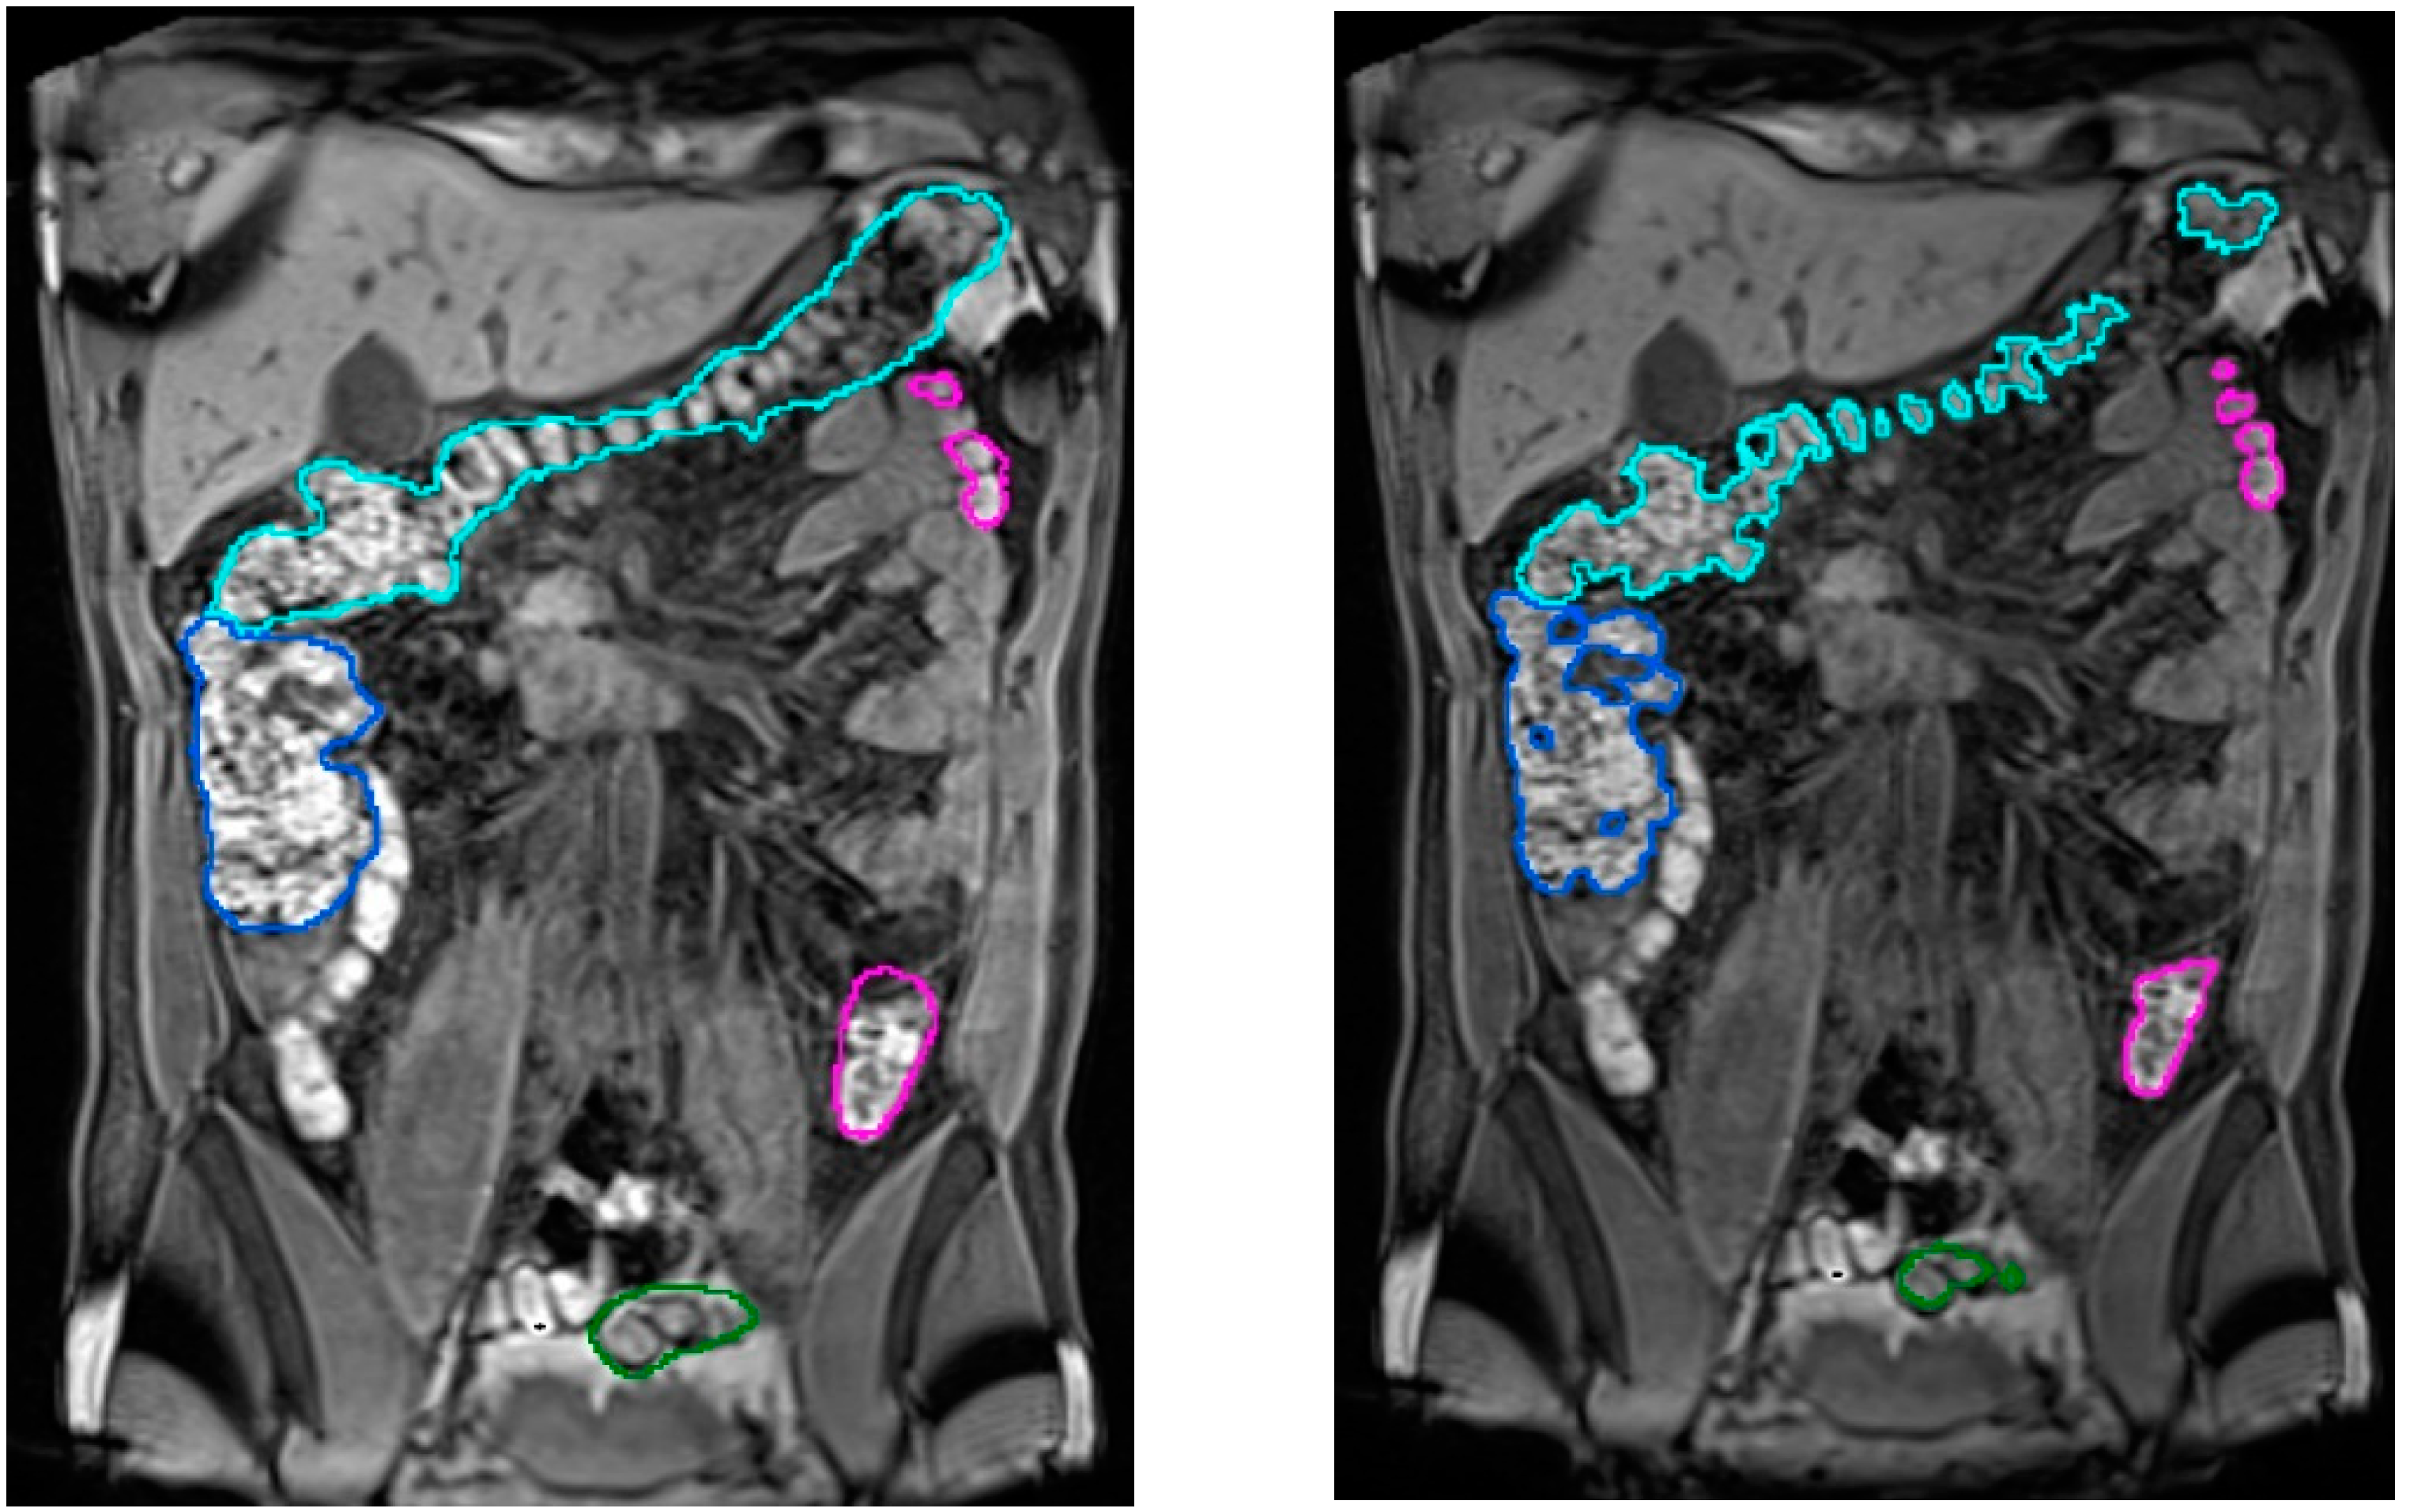

The validation of the colon segmentation from T2 images was presented in [7]. In total, 52 scans were used in the accuracy experiment: 30 scans from 15 healthy participants (8 women, 7 men) and 22 scans from 11 patients (8 women, 3 men) with irritable bowel syndrome (IBS); participants had a normal body mass index or were overweight (body mass index between 18.5 and 29.9 Kg/m2), i.e., no underweight or obese subjects were included. The assessment of the algorithm accuracy was performed by comparing the segmentation results to the ground truth (specialist manual segmentation) using the dice similarity coefficient (DSC). The achieved accuracy was (µDSC = 0.85, σDSC = 0.06), demonstrating its suitability for clinical usage. Figure 4 compares results of the colon segmentation computed by the algorithm with respect to a ground truth segmentation manually performed by the medical expert. In the left image, the medical expert did not realize that a small ileum region had been wrongly identified as colon by the segmentation algorithm. This misclassification was probably due to a similar pixel intensity in both the ileum and the adjacent colon, which made it very difficult to identify the colon in that area. As explained in Section 3.2, a simultaneous visualization of the T1-FS images could have helped him to fix this wrong identification. From the point of view of performance, the average execution times (in minutes) for all the volumes involved in the experiment were in the range 5.7 ± 1.16 min, with a maximum peak of 8.5 min, and the memory usage was below 2.5 GB. Focusing on the usability of the process, the experiments demonstrated that this approach could be considered as low demanding in terms of user time (on average 5′ of usage time). Compared to the initial approach presented in [12], usage times have been reduced by 80%.

Figure 4.

Comparison of segmentation results (in blue) with a ground truth manual colon segmentation (in green) in T2 images. In the left image, the red arrow marks a small ileum region wrongly assigned to colon by the automatic algorithm. In the right image, a highly challenging area even for the specialists (outlined in red) is shown. Courtesy of [7].